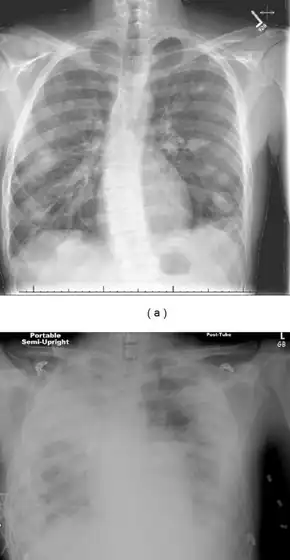

Top: Pulmonary nodules and infiltrates Bottom: Develops into dense bilateral infiltrates and ARDS

Chest X-ray and chest CT may show pleural effusion, nodules, infiltrates, abscesses and cavitations.